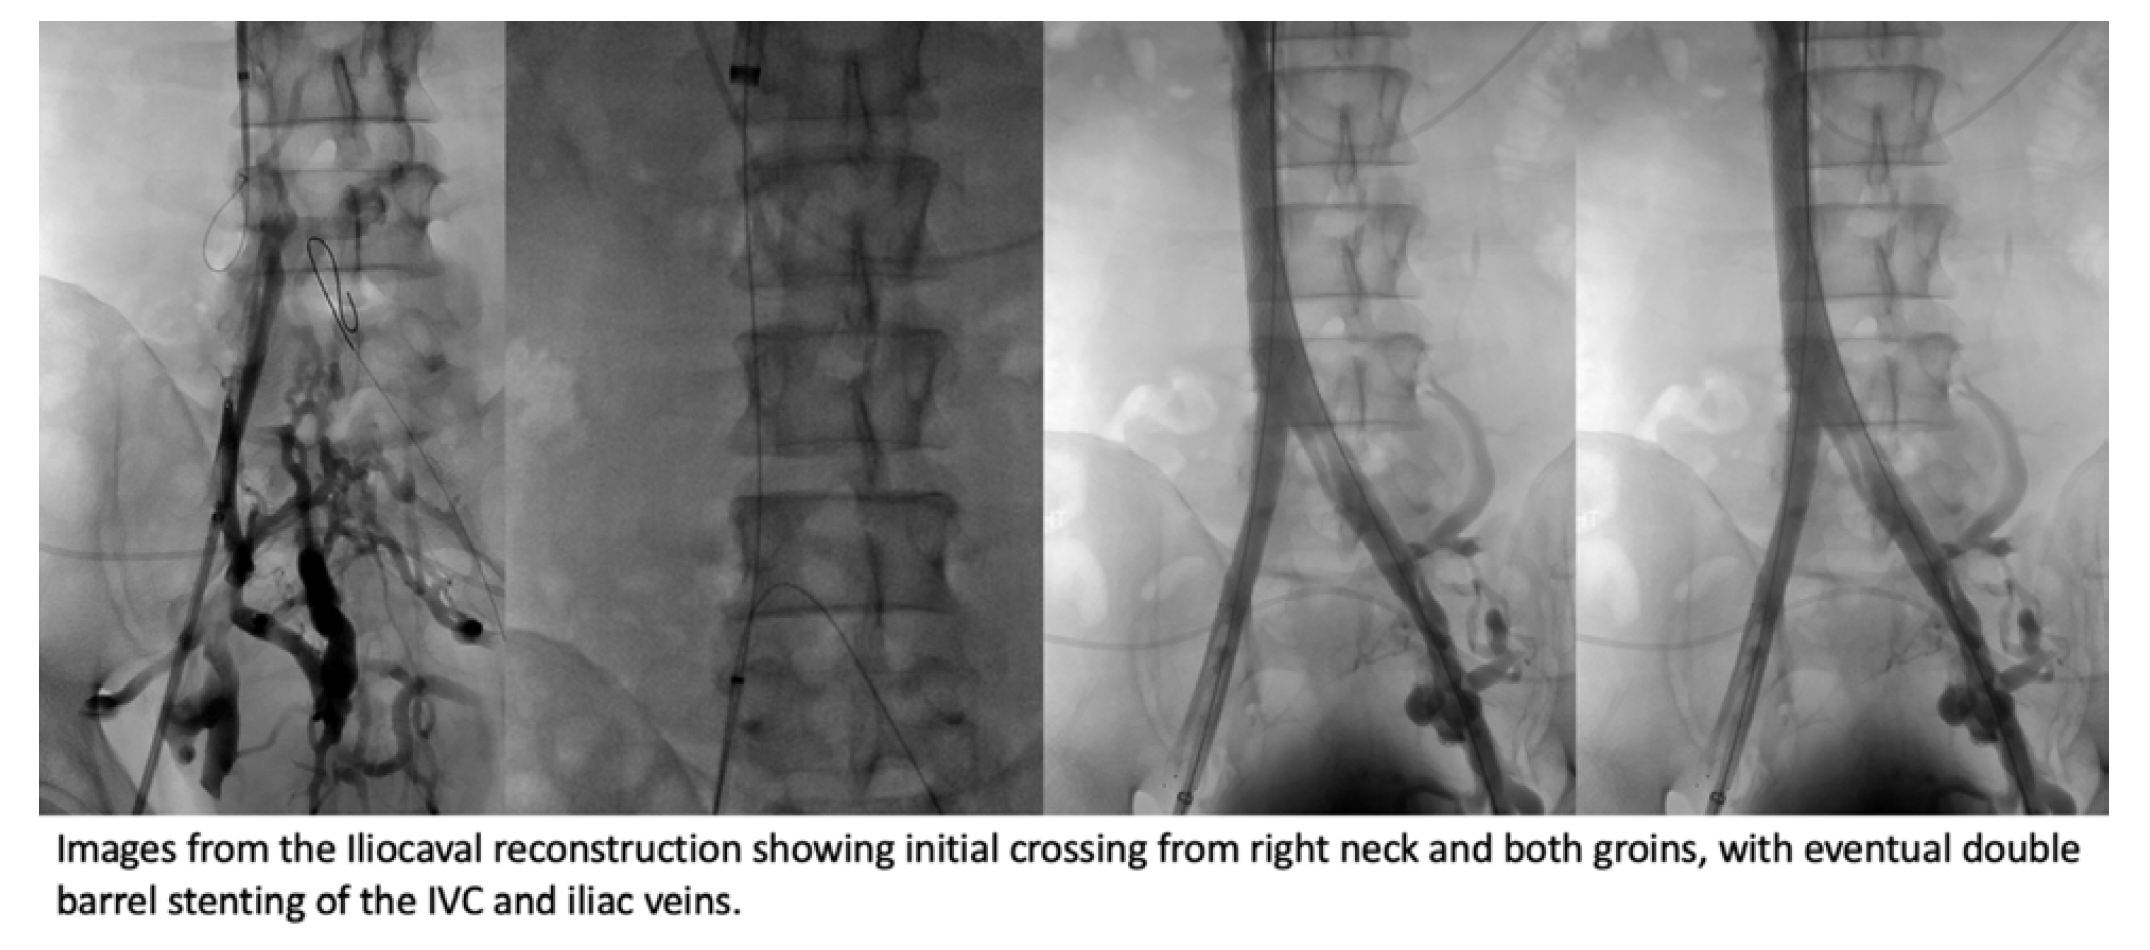

Complex IVC Filter Removal With Iliocaval Occlusion

As described above, a well-known complication of long-term indwelling IVC filters is thrombosis of the venous system and possibly chronic occlusion. This can be a very complex situation as the decision has to be made whether to attempt a complex IVC filter removal and iliocaval reconstruction. This should be a carefully assessed approach. Once chronically occluded, it may be prudent to leave the filter in place and not pursue reconstruction if the patient is not symptomatic, as they may have collateralized sufficiently and may be able to tolerate mild symptoms such as minimal swelling. However, patients with such situations can be found to have post-thrombotic syndromes; these are especially troubling for patients with nonhealing or recurrent venous ulcers of the lower extremities, which can be debilitating and often take months to years of wound care and have other complications. Other indications may include venous claudication, symptomatic varicose veins, etc. If the intervention is undertaken, the decision also includes whether to perform exhaustive attempts to remove the embedded IVC filter, to potentially stent through and exclude the filter. There are no definitive data regarding which method provides the best outcome; however, we feel that if the filter can be removed, it should be, and this may reduce issues with pushing the filter against the caval wall (conical filters) by the stent scaffolds, which may cause additional caval perforation and symptomatic irritation of adjacent structures. If the proximal and/or distal aspect of the filter can be controlled, we feel it should be removed. If extracaval or in some instances with the polyhedral filters, it may be easier to stent through the filter. Regardless of approach, good preoperative cross-sectional imaging, frank discussions with patient/family and referrers, and access and experience with advanced techniques are recommended.

Example Case of Iliocaval Occlusion with IVC Filter

The patient is a septuagenarian male with a history of stroke and an incidentally found IVC filter, which he was not aware of 12 years earlier when he was being worked up for abdominal pain and lower extremity venous ulcers. The patient had a CT scan, which showed iliocaval occlusion with collateral formation, and he was planned for intervention. Post procedure, the patient experienced improvement of abdominal pain and eventual wound healing of the lower extremity. His venous insufficiency has been managed lifelong with compression therapy and other conservative measures.